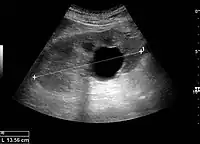

Figure 5. Simple renal cyst with posterior enhancement in an adult kidney. Measurement of kidney length on the US image is illustrated by '+' and a dashed line.[1]

Figure 6. Complex cyst with thickened walls and membranes in the lower pole of an adult kidney. Measurements of kidney length and the complex cyst on the US image are illustrated by '+' and dashed lines.[1]